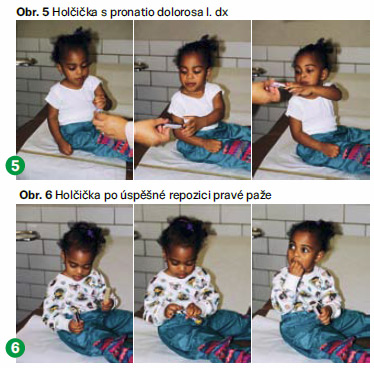

Subluxace hlavičky radia se léčí repozicí. Je to rychlá a jednoduchá procedura nevyžadující sedaci. Provádí se ihned po stanovení diagnózy, což zabrání prodlevě a rychleji se odstraní bolestivost a úzkost u dítěte. Repozice je snadná ve flexi lokte při současné supinaci. Je znatelný repoziční fenomén (slyšitelné lupnutí), přeskočení a okamžitá úleva od bolesti (a úplné vymizení obtíží). Lékař může naordinovat krátkodobé zklidnění končetiny. Při recidivách je někdy zapotřebí končetinu fixovat sádrou na dva týdny. K případnému tišení bolesti se podávají volně prodejná analgetika, jako je Paralen a Ibuprofen.

Samotná repozice se provádí tak, že lékař pevně uchopí postižený loket jednou rukou, aby ho imobilizoval a nahmatal hlavičku radia (obvykle palcem). Zatímco vyvíjí tlak v blízkosti vrcholu radia, druhou rukou uchopí zápěstí postižené končetiny a zatímco supinuje předloktí, provede pomalou flexi lokte. Po přeskočení může být cítit či slyšet lupnutí či prasknutí v místě hlavičky radia, což potvrdí správné přemístění hlavičky do kloubu. Manévr trvá pouze několik sekund a může být bolestivý. Děti obvykle při repozici pláčou. Bolest poleví po uvedení kosti zpátky do správné pozice. Někdy se repozice nezdaří na první pokus a je potřeba ji opakovat dvakrát i vícekrát. Chirurgická léčba se provádí jen výjimečně. Je-li repozice po dvou až třech pokusech neúspěšná a pokud se čeká na návrat normální funkce končetiny, je nutné provést RTG vyšetření. K zabránění recidivy subluxace hlavičky radia je po repozici nezbytná edukace rodičů, prarodičů, sourozenců a pečovatelů.

Po provedení repozice lékař zkontroluje neurovaskulární stav postižené paže. Většina dětí začne používat končetinu bez pocitu bolesti téměř okamžitě či během několika minut po zákroku (nebo v průběhu následujících 10–15 minut po něm). Jestliže dítě stále váhá použít poraněnou končetinu, lékař počká několik minut, aby došlo ke zklidnění dítěte, a nabídne mu nějaký předmět (omalovánky, sladkost). To může povzbudit dítě, aby začalo používat zraněnou končetinu. Některé děti mohou mít strach končetinu použít, protože si pamatují její předchozí bolestivost. Pokud k tomu dojde, lékař může naordinovat analgetika a dítě je v čekárně sledováno po jednu následující hodinu, zda začne hýbat paží.

Bolestivost může přetrvávat až 24 hodin, než kompletně odezní a dítě znovu začne končetinu plně používat. U dětí pod dva roky věku a kde je přítomno prodlení trvající více než čtyři hodiny před provedením repozice, může návrat normální funkce trvat déle. Některé děti trpí vykloubením hlavičky radia opakovaně. V těchto případech může lékař naučit provedení repozice rodiče nebo příbuzné dítěte.

Pokud je repozice úspěšná a dojde po ní k napravení funkce loktu, nebývá následná kontrola většinou nutná. V některých případech je nutná kontrola lékařem po 24 až 48 hodinách. Lékař může naordinovat zklidnění končetiny v závěsu (šátku). Někteří pacienti, u kterých nedošlo k navrácení funkce do půl hodiny po repozici, dosáhnou plné funkce kloubu do čtyř dnů od provedení zákroku.